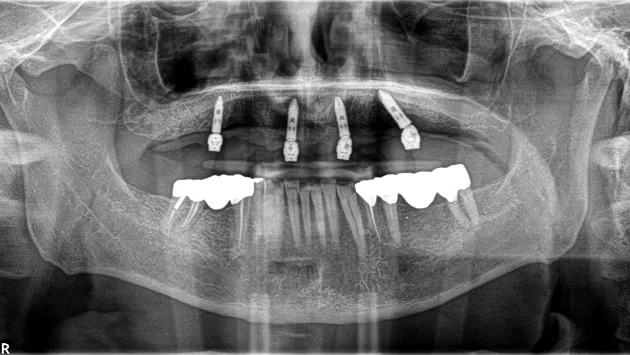

Un especialista revisará el estado de tu boca con radiografías, fotos panorámicas, un escaneo 3D (CBCT), entre otros estudios. Con eso, te dará las mejores opciones de tratamiento.

La cirugía normalmente no duele. Se extraen las piezas dentales necesarias y, usando la tecnología Navident, se colocan los implantes. Si no se usa Navident, se trabaja con una guía quirúrgica.